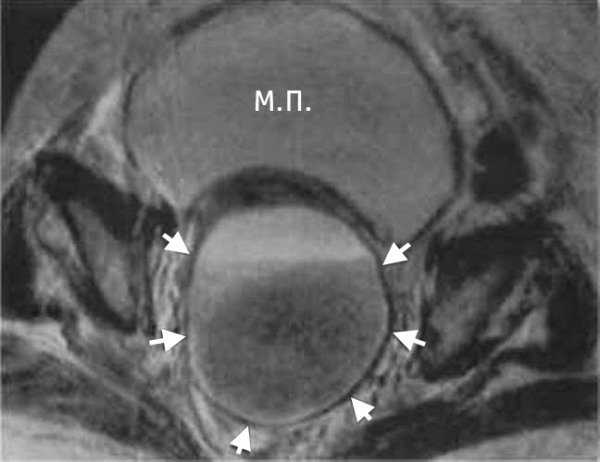

КТ-исследование абсцесса малого таза: Визуализация и диагностика

Раздел: Фотоальбом решений